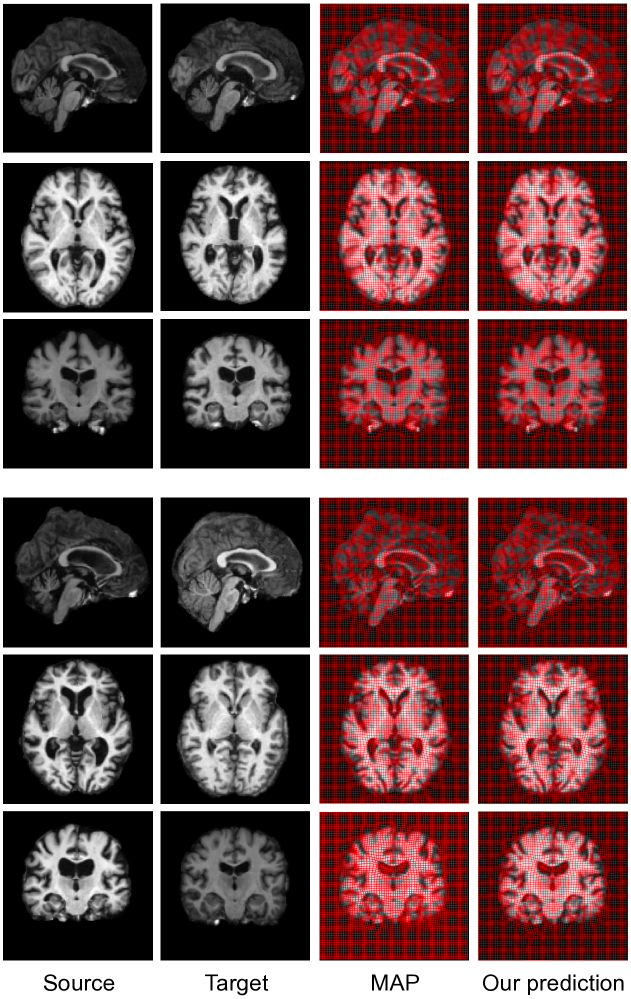

Fig. 6 displays deformed 3D brain images overlaid with transformation grids for both methods. The parameter estimated from our model produces a comparable registration result. From our observation, a critical pattern between the optimal αoptsuperscript𝛼𝑜𝑝𝑡\alpha^{opt} and its associate image pairs is that the value of α𝛼\alpha is relatively smaller when large deformation occurs. This is because the image matching term (encoded in the likelihood) requires a higher weight to deform the source image.

Refer to caption

Figure 6: Left to right: source, target, deformed images overlaid with the transformation grids generated by both methods. The optimal and predicted value of α𝛼\alpha for two showcases are (8.90,9.20)8.909.20(8.90,9.20) and (3.44,2.60)3.442.60(3.44,2.60).